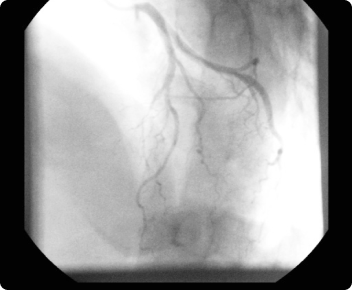

弁やその周りの石灰化、血液循環の状態を調べます。